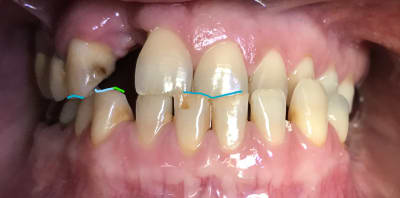

> Tu me conseilles quoi pour ce cas ?

Allez j’ai fait des empreintes d’etude :))

Elle a la gueule de travers . Donc faut bien lui replacer tout ça avant ... c’est pour ça que j’attendais qu’Enlaye nous fasse un petit topo.

Vous pensiez que j’allais faire les prothèses comme ça :))) , hein ? Tel est pris qui croyait prendre :) une petite perche et un hameçon lancé et op on embarque du monde :)